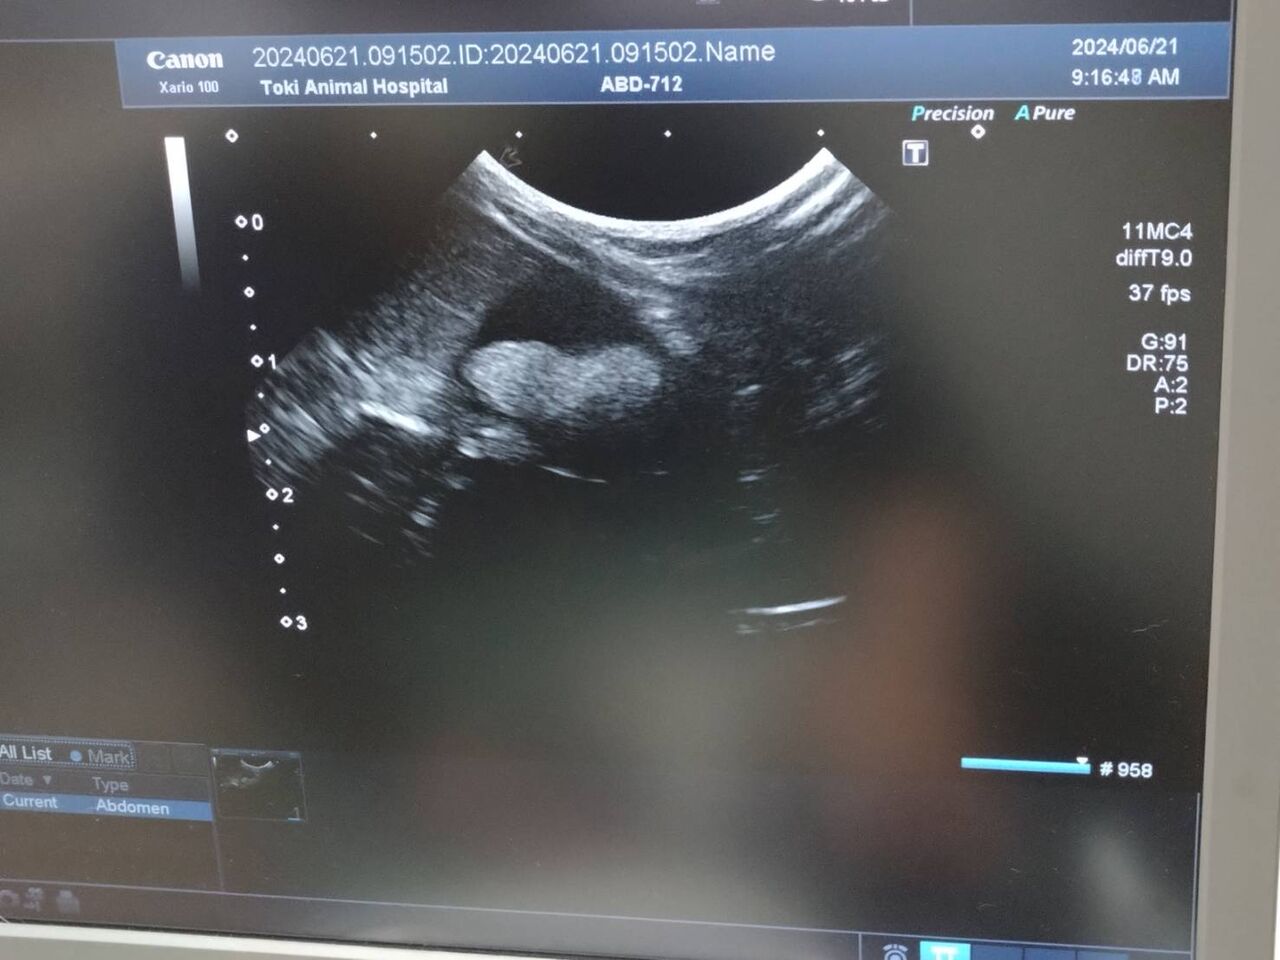

6/21 体重1820g

前回の通院後の様子を確認するため通院

再度エコー検査を行いました

膀胱下にたまっていた砂が大きな2つの塊に変化

元々お水を飲む量が少ないので、今後は水分の多い野菜で対応していく方向になりました